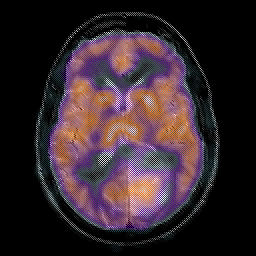

Glioma overlay -- Slice #15

[Home][Help][Clinical] Slice 15